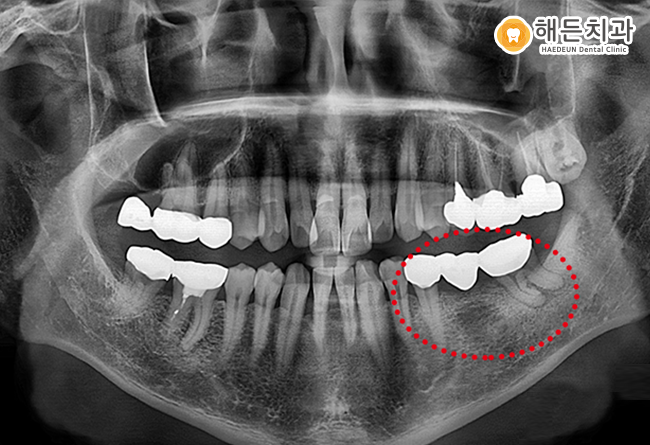

해당 이미지는 임플란트 계획 수립을 위해

해든치과에 내원한 환자분의 엑스레이 자료로,

아래쪽 어금니 부위에 문제가 확인된 상태였습니다.

해당 환자분의 경우 기존에 브릿지로 연결된 상태였으며,

이를 제거한 이후 양쪽 치아는 상태에 따라

신경치료를 진행하는 방향을 고려했습니다.

가운데 결손 부위는 천안아산치과에서 임플란트로

보완하는 계획을 세우게 되었습니다.